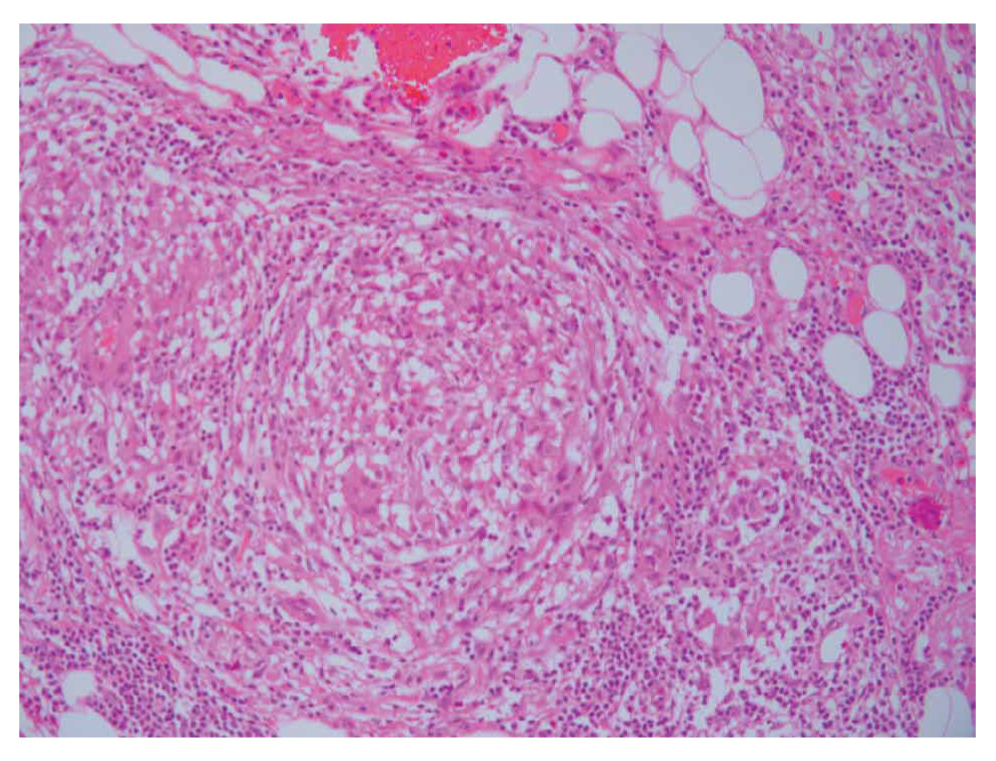

The CT that he brought showed a mass lesion in the head of the pancreas (Figure 1A, 1B) measuring 4.0 x 4.5 x 4.1 cm. No other imaging tests have been performed. The EUS revealed a hypoechogenic compact mass with homogeneous texture and longest diameter approximately 4cm, which did not infiltrate the main pancreatic duct, the common bile duct or important blood vessels. The extra-hepatic bile tree was normal. There were no lymph nodes near the pancreas or hepatic lesions that were suspected of metastasis (at the region that we could examine). EUS-FNB performed through the stomach, with a 22-gauge needle, was performed. Pathology test revealed a rare diagnosis and particularly: necrotic granulomatous inflammation, composed of central necrotic zone surrounded by epithelioid histiocytes with varied numbers of multinucleated giant cells and lymphocytes (Figure 2 and 3). Finally, Ziehl-Neelsen staining revealed the diagnosis of pancreatic tuberculosis (Figure 4A, 4B).

Figure 2. Central zone of necrosis.

Figure 3. Epithelioid histiocytes with multinucleated giant cells and lymphocytes.